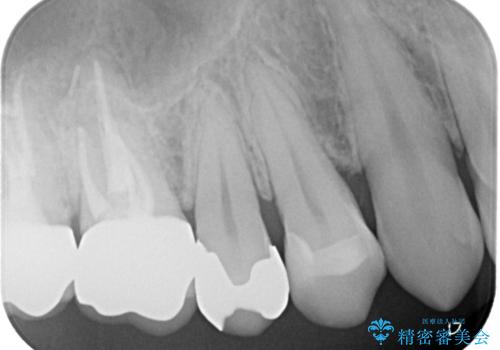

他院のセラミックインレー やり直し治療

- 以前、他院で入れたセラミックインレーが欠けてしまっているとのことでご来院されました。内部に虫歯が無いかどうか確認したうえで、割れにくいように形を工夫して新しいセラミックインレーをセットしました。術後の経過は良好です。

セラミック自体が薄すぎる場合や、十分な厚みがある場合でも局所的に強い力がかかるとセラミックは割れてしまいます。今回の患者様のセラミックが欠けてしまった要因は、おそらく歯並びの問題で、その歯に日常的に過剰な力がかかっていたためだと予想されます。割れたセラミック自体は基本的につなぎ合わせられないため、作り直しになります。今後同じことが起こらないようにするために、根本的に歯列矯正を検討しても良いかもしれません。